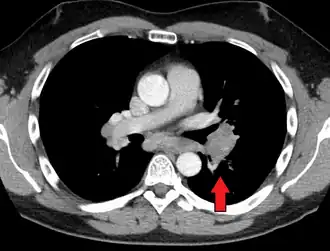

-

Hilar adenopathy especially on the person's left (transverse CT)